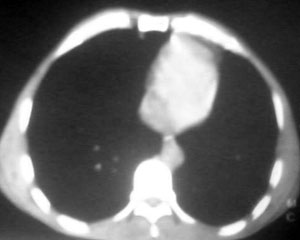

以下是引用逸风在2006-9-12 14:57:00的发言:[br]ct显示双肺上叶点片状及纤维索条状密度不均影,肺野外带近胸膜可见大小不等的含气空腔,壁略厚,境界清晰,未见液平面,中下肺野散在小片状及点状高密度影;纵隔内显示点状钙化,未见明显淋巴结肿大,构成胸廓诸骨未见明显异常.[br]诊断意见:1.双肺结核合并支气管播散;2.双肺上肺大泡.